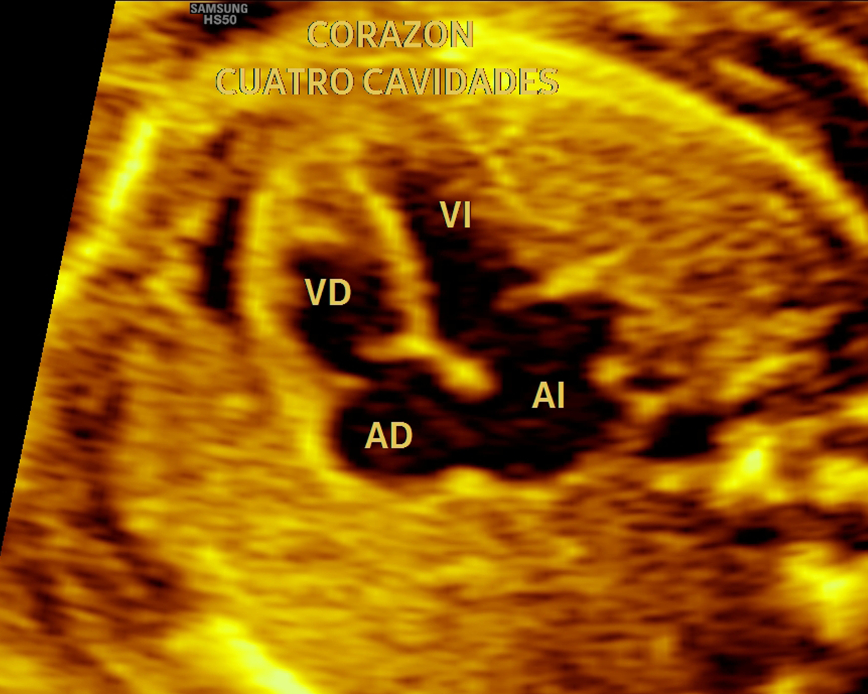

Con nuestra tecnología 5D y 6D de alta resolución, podrás ver la carita, las manos, los pies, la columna y el sexo de tu bebé con imágenes de alta calidad. Además, podrás apreciar los gestos de tu bebé en tiempo real. Esta ecografía también nos ayuda a detectar las malformaciones congénitas que pudiera tener el feto.